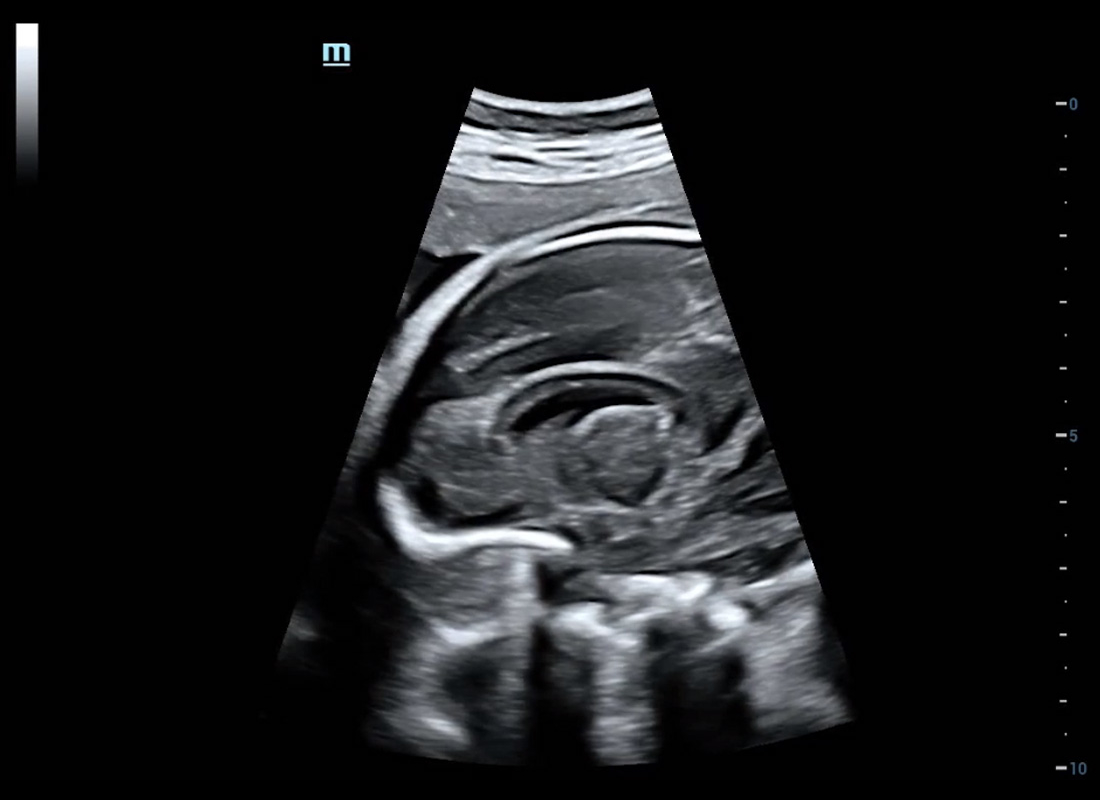

Central nervous system (CNS) malformations are one of the most common congenital abnormalities. Unfortunately, due to imaging limitations such as poor fetal position, acoustic shadowing, and operatorsŌĆÖ poor scanning skills, the MSP is particularly difficult to find in a 2D ultrasound. In this case, a faster and more user-friendly method, which automatically displays the standard planes together with the required measurements in a fetal CNS examination, could significantly boost both the quality and efficiency of clinical diagnoses.?NuewaŌĆÖs intelligent solution of fetal brain can realize automatic acquisition of brain volume data based on intelligent recognition of CNS application scenarios, intelligent generation of four fetal brain standard planes including MSP, automatic measurement of CNS biological items and automatic evaluation of fetal brain volume. More importantly, Nuewa's leading color Doppler technology can provide a clear and sensitive dynamic display of blood flow in the tiny vessels.